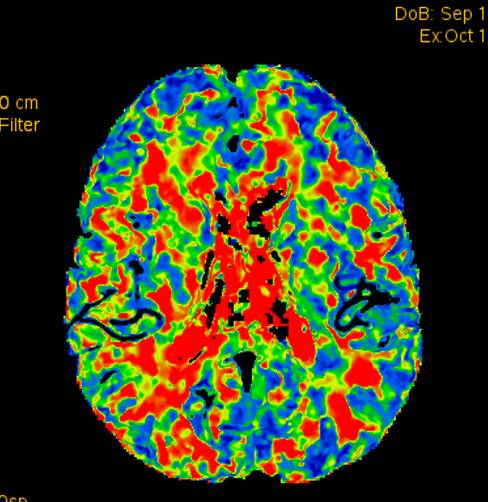

术前灌注成像,右侧大脑半球灌注较差。

此次分享两例颈动脉闭塞复合手术开通病例。第一例为颈内动脉长段闭塞,从颈内动脉起始段开始闭塞。患者术前存在眼动脉缺血事件及右侧半球灌注不足。颈内动脉剥脱后,颈内动脉可淡淡显影,为微导管通过创造条件。微导管通过后,顺利完成球囊扩张及支架植入,完全开通右侧颈内动脉。第二例为右侧颈总动脉闭塞患者,虽有颈外动脉代偿,但仍存在TIA及右侧大脑半球灌注不足。经颈动脉内膜剥脱后,造影可见颈总动脉显影,但管腔严重不规则,经球囊扩张及支架植入后,颈总动脉显影好。两例患者术后7天复查颈动脉CTA,均显示颈内动脉起始处较术后造影增粗。